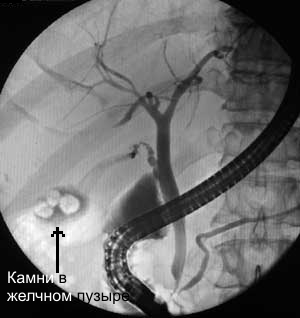

Рентгеноскопия желчного пузыря   Рентгеноскопия - это медицинский метод рентгенологического исследования, основанный на получении рентгеновского изображения (фотографии) на флюоресцентном экране рентгеновской установки или на телевизионном экране.

Рентгеноскопия используется при лечении заболеваний желудка, желудочно-кишечного тракта, 12-перстной кишки, заболеваний печени, желчного пузыря и желчевыводящих путей. При этом медицинский зонд и манипуляторы вводят без повреждения тканей, а действия в процессе операции контролируются рентгеноскопией и видны на мониторе.